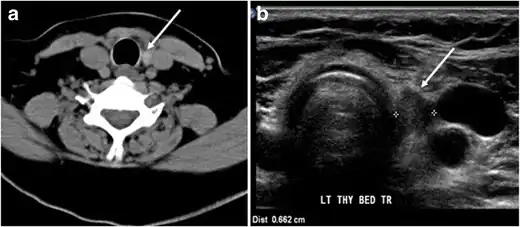

Fig. 14. A 19-year-old male patient known to have multi-nodular goiter and FNA, showing underlying Hashimoto's thyroiditis. a, b Sagittal and transverse greyscale and colour Doppler ultrasound of the neck demonstrate a hypoechoic enlarged right thyroid lobe with small hyperechoic regenerative nodules and marked hypervascularity (white arrows). c, d Enhanced axial CT scan images of the neck demonstrate a heterogeneously enhancing and enlarged thyroid gland, left more than right lobe, and the trachea is markedly narrowed.[1] -